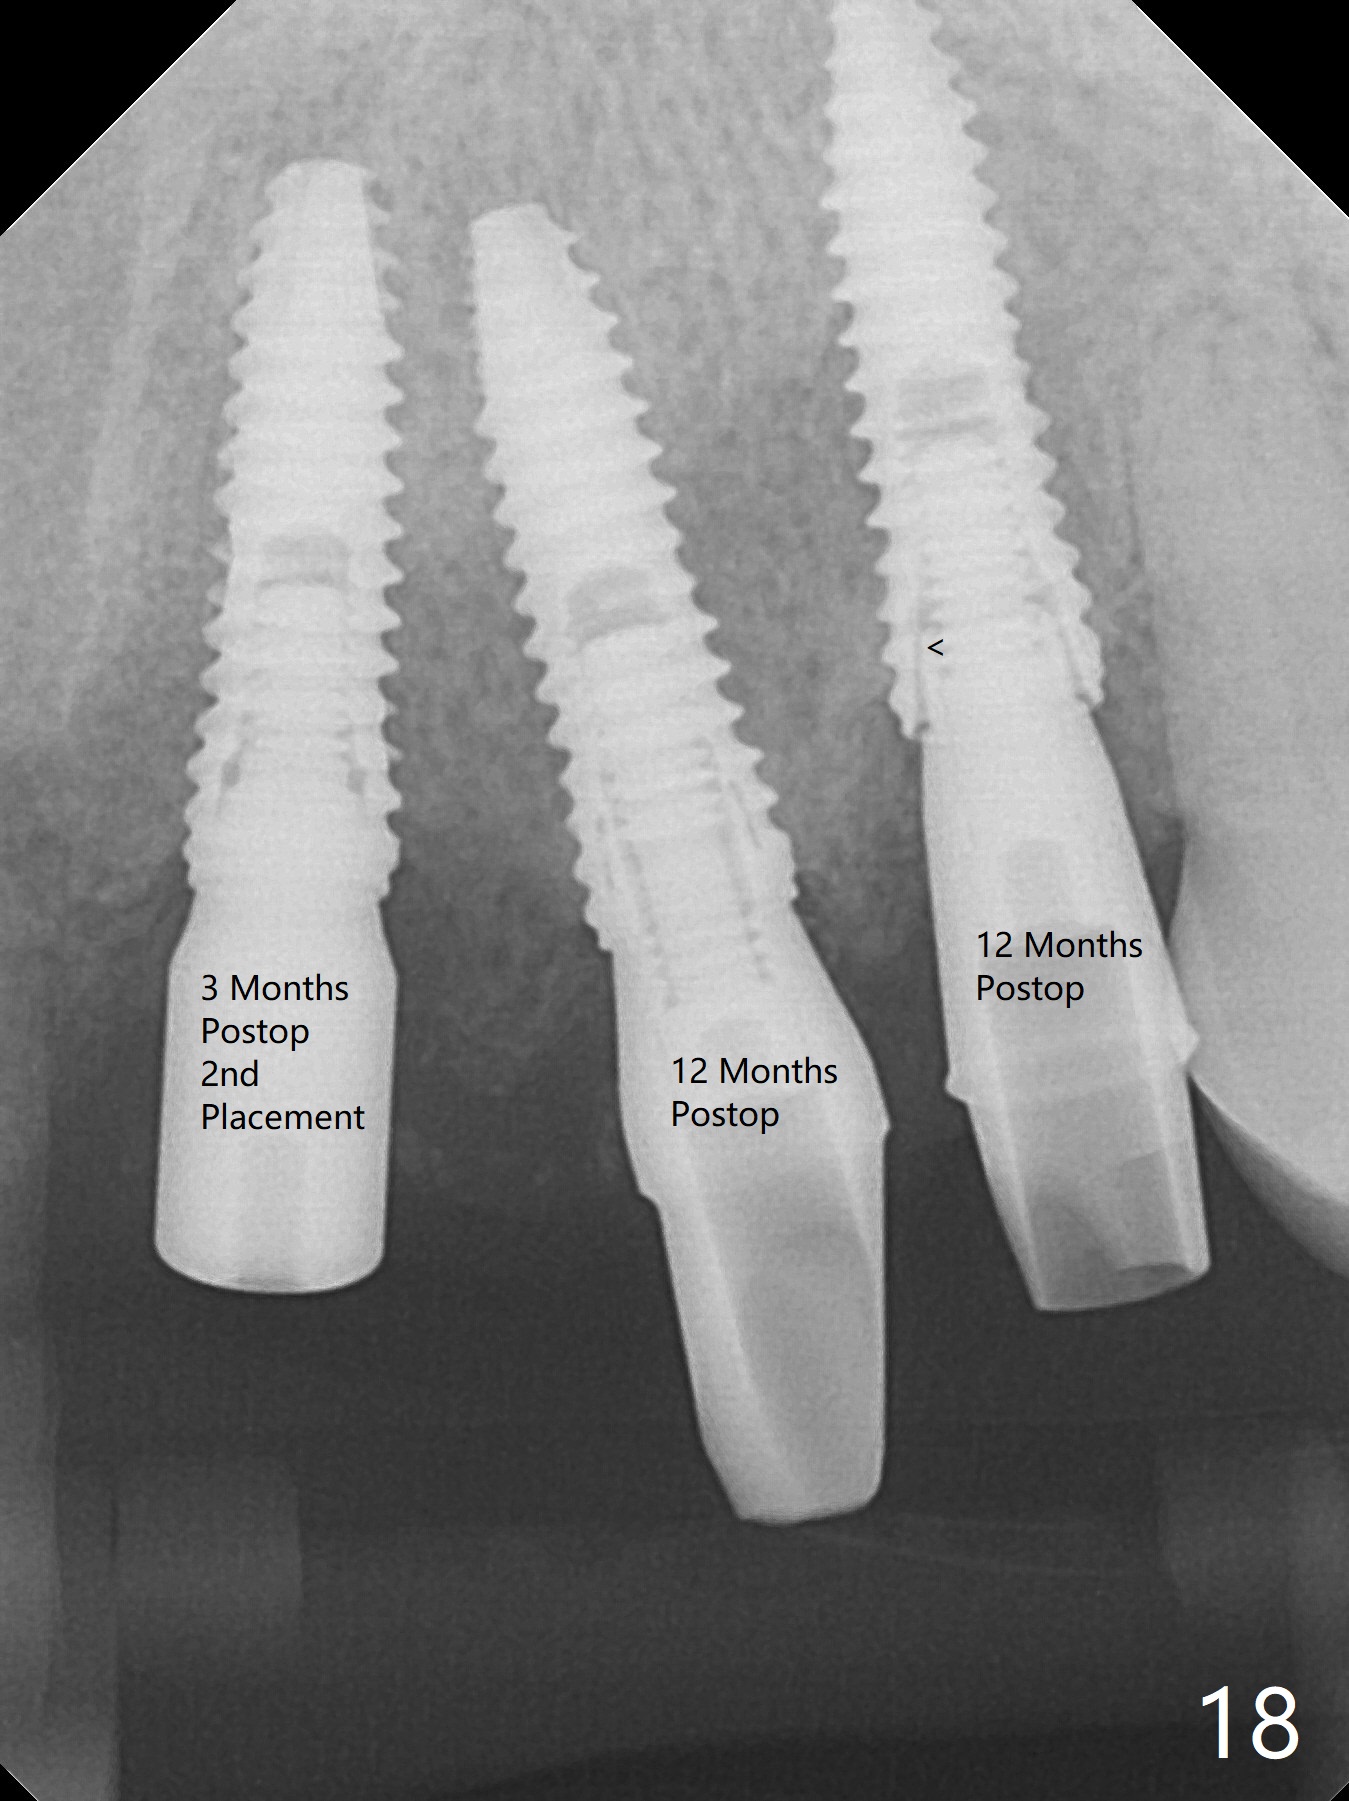

To have enough clearance for the splinted provisional at #6-12 (Fig.1 *), composite has been placed in the posterior teeth (bilateral, *, Fig.2). When the composite is removed, there is no clearance between the implants/abutments of #7 or 10 (Fig.3). Incision is made with removal of the 1-piece implant at #7; there is enough bone to move the osteotomy buccal (Fig.4 arrowhead). When the same implant is placed buccal (Fig.5), there is sufficient clearance for restoration (Fig.6 *), while there is still enough buccal bone left (Fig.7). When the patient returns 5.5 (for #7 and 10)/6.5 (#6,11,12) months postop, his chief complaint is tenderness lingual to #11. In fact, the abutment screw is loose at #11, while the implant at #10 has mobility (Fig.8), which is related to loss of the posterior stops (*) due to wear. There is slight bone loss mesial to #10 implant 5.5 months postop (Fig.10, as compared Fig.9). CBCT taken 5.5/6.5 months postop shows no bone loss (Fig.11-15). The 3x14 mm 1-piece implant at #10 is mobile 9 months postop and is removed and replaced by a 3.5x13 mm 2-piece one with slightly buccal osteotomy (Fig.16). PAs are taken prior to impression (Fig.17,18). The abutment at #12 is loose (<). More composite needs to be added to the occlusal surface of the upper posterior teeth. Finally the patient agrees to have crowns for the upper posterior teeth.